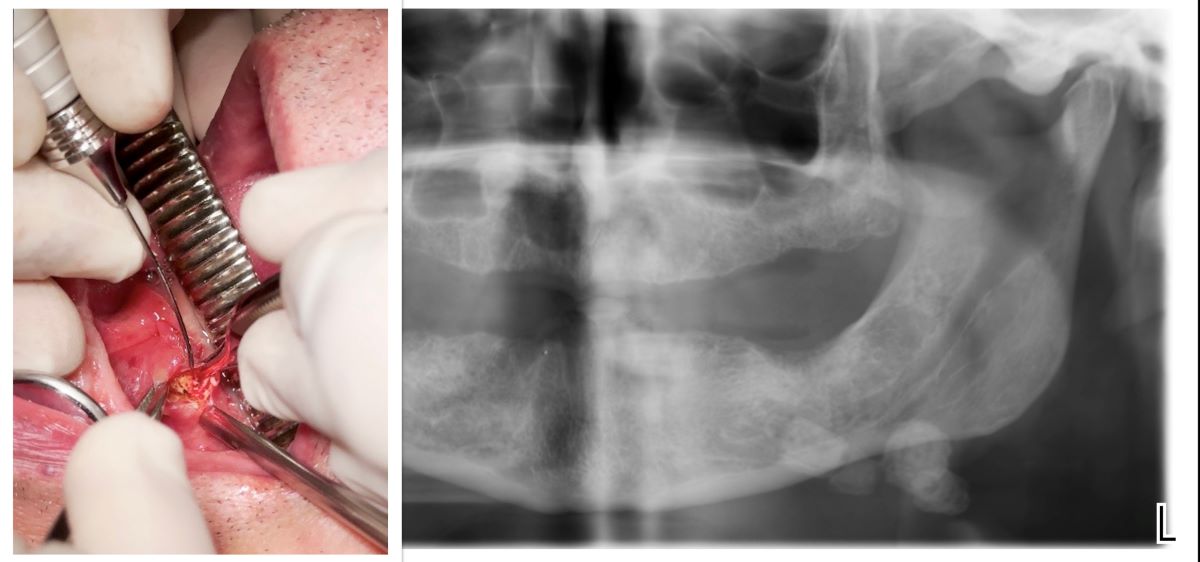

| Haas OL H. et al. (2018) [14] | Case series | 2 cases, 1 M: 33 Y 1F: 93 Y |

Distal part of the submandibular duct and could be palpated intraorally. | Diode laser | 400-μm optical fiber emitting at a wavelength of 980 nm (infrared), 2.5 W output power, and in continuous pulse mode. | Amoxicillin (500mg) every 8h for 7 days and oral acetaminophen (750 mg) every 6h for 3 days | No intraoperative complications were reported | Evaluated on days 7,14, and 30 free surgery. | The diode laser is a safe, minimally invasive option for this procedure, offering enhanced coagulation, high-quality incisions, no bleeding, low nerve damage risk, and minimal comorbidities |

| Mathew J et al. (2022) [15] | Case report | 1 case, 1M: 50 Y |

Behind the lower right second permanent molar | Diode laser | 810 μm | - | Asymptomatic with undisturbed salivary flow | One year. | Newer treatment modalities offer effective alternatives to conventional surgical methods for sialoliths. |